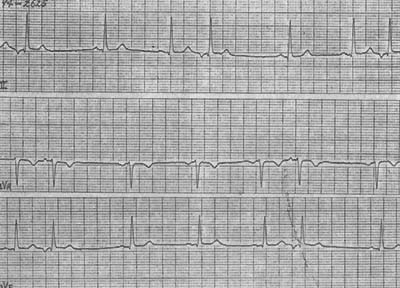

圖2 頻發房性早搏伴室內差異性傳導

頻發房性早搏(標記A)提前的畸形P′在前一次心搏T波上,下傳QRS波與竇性不同的為室內差異性傳導,第一個和第八個標記A其後無QRS波為阻滯性房性早搏